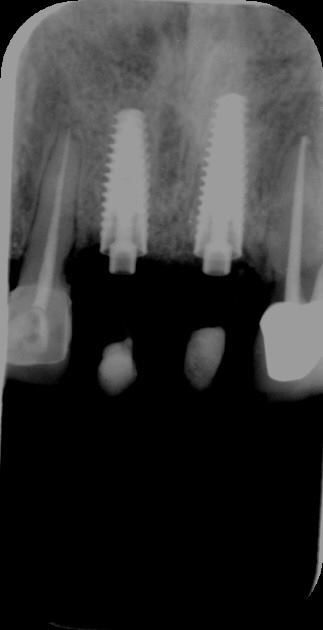

![]() |

Hình ảnh trong miệng và X-quang của khách hàng làm cầu răng sứ trên implant